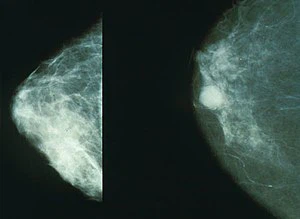

오늘은 유방암 초기 증상에 대해 살펴보겠습니다. 유방암은 가슴에 발생한 암을 의미합니다. 유방암 진단을 받는 환자의 수는 한 해 동안 2만 명에 달하고, 여성들한테 제일 흔한 암 중 하나입니다. 2019년 이전까지 1위였던 갑상선암을 넘어 유방암이 여성 암 유발률 1위에 올랐습니다. 가슴에 응어리(멍울)가 만져지고 진통이 생기게 되면 어쩌면 유방암 초기 증상일 수 있습니다.

유방암은 유방조직에 악성 세포 암이 발생하는 것을 의미합니다. 유방조직이 적은 남자 또한 유방암에 걸릴 수 있습니다.

유방암은 일반적으로 남자보다 여자한테 자주 발생하고, 매해 발생률이 약간씩 늘고는 있지만 정확한 이유은 아직 확실히 알려지지 않았습니다. 생활환경이나 유전적 요인 정도로 발생한다고 알려져 있습니다.

유방암 초기 생존율

유방암은 0~4기로 구분합니다. 다른 암과 마찬가지로 4기로 갈수록 말기이며, 각 시에서도 A에서 C등급으로 구분합니다. 유방암 초창기에 속하는 0기인 유방암 초기의 생존율은 약 98퍼센트가량으로 예후가 좋은 편이고, 1기는 96퍼센트 수준의 완치율입니다. 유방암 2기 생존율은 92%, 3기 75%, 4기에 발견시 34%의 생존율을 보이고 있습니다.